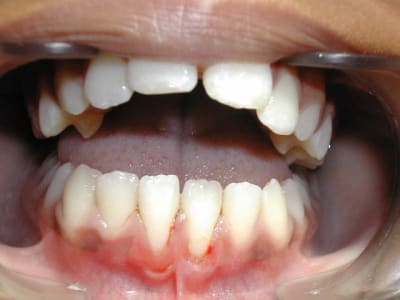

Voici un cas de béance associé à un Pb. paro sur 31/41

Est-ce qu’un traitement ODF. ne vas pas aggraver cette perte de gencive attaché (et osseuse),

et faut-il faire des extractions pour replacer 31/41 dans le massif osseux et arrêter cette récession ?